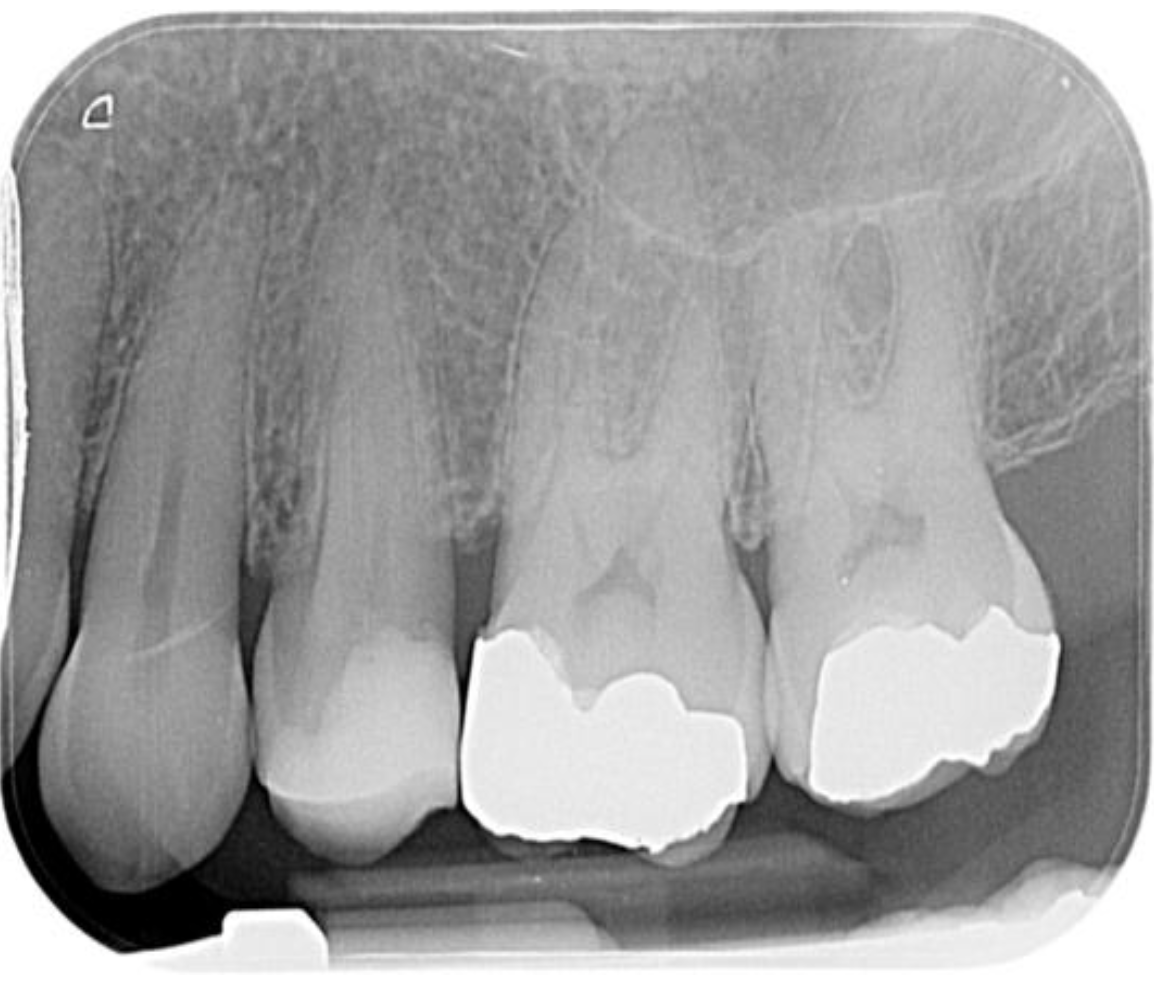

This upper second premolar Vertucci type 4 case was diagnosed with SIP and no clear apical change on IOPA.

It was prepared using 1403, 2004 and 2504 VS Flexi files from Toothsaver, as the canals appeared narrow and calcified on the pre-op IOPA. It was obturated with Onefill BC sealer and hydraulic condensation. On the post-op radiograph, you can see how the sealer-based obturation has filled the apical bifurcation of the buccal canal really nicely, which should help to achieve a positive outcome.